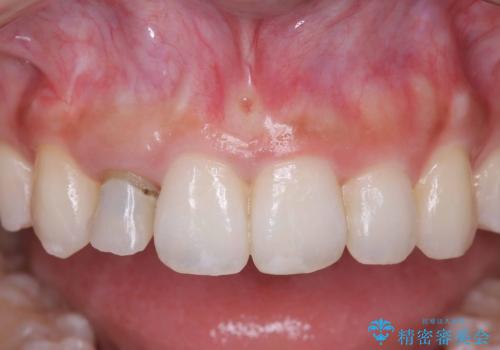

- 「前歯の見た目が気になる」を主訴に来院された患者様です。

オールセラミッククラウンで治療を行いました。

被せ物と歯の境の位置が歯肉の上に設定されており、それによって審美障害が起きていました。

歯と被せ物の境を歯肉縁下0.5㎜に設定して形成を行いオールセラミッククラウン(スペシャル)で治療を行いました。